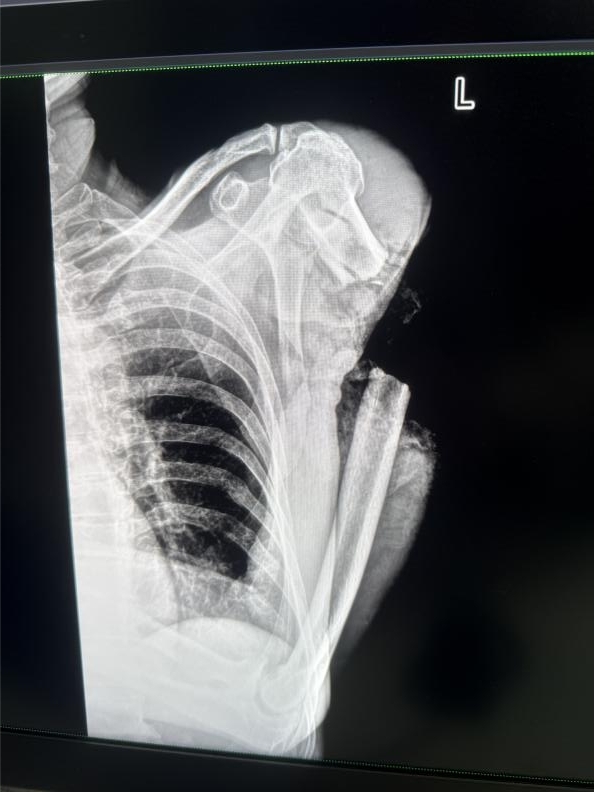

CT圖像下冉文海斷臂情況非常嚴峻。張曉銳供圖

“左上臂已經完全離斷,上臂上段呈環形開放性傷口,僅僅部分皮膚、肌肉相連,重要血管神經毀損長度達8厘米,污染物深入肌理,這比兩年前張志偉病例更兇險的高位離斷。”手術醫師張曉銳回憶,團隊果斷啟用“創傷優先分級救治系統”,在患者仍處于休克狀態時,已同步完成離斷肢體低溫處理、三維CT血管成像和手術方案制定。